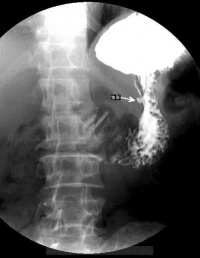

- X线钡餐检查:溃疡的X线征象有直接和间接两种:龛影是直接征象,对溃疡诊断有确诊价值。良性溃疡凸出于胃、十二指肠钡剂轮廓之外,在其周围常见一光滑环提,其外围辐射状粘膜皱襞。间接征象包括局部压痛、胃大弯侧痉挛性切痕、十二指肠球部激惹和球部畸形等,间接征象仅提示有溃疡。